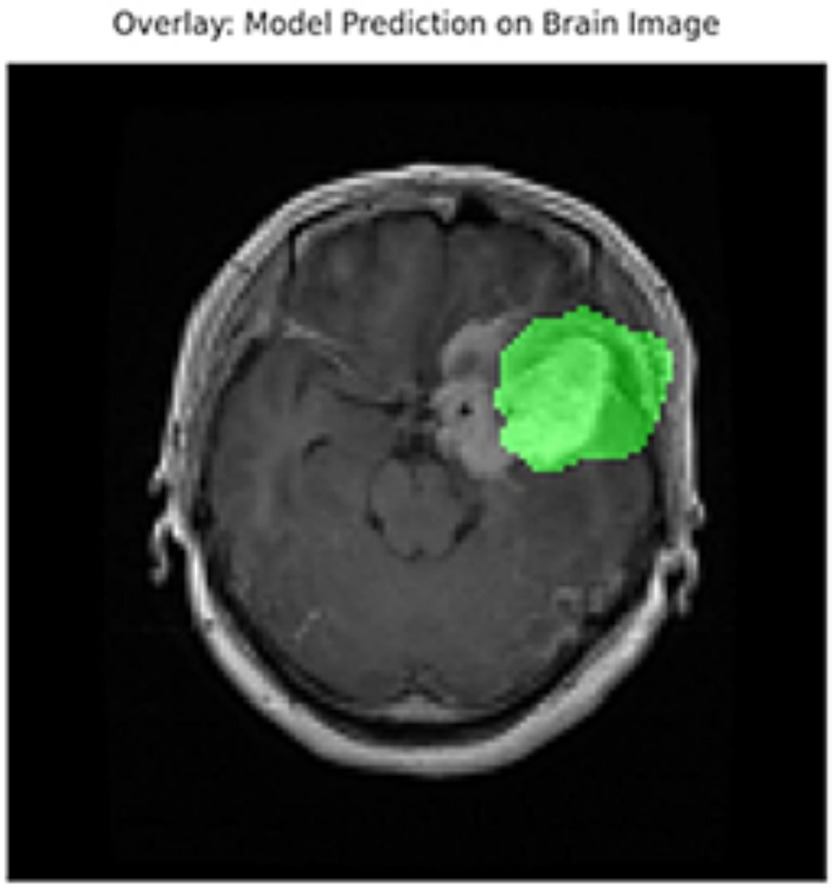

In addition to quantitative metrics such as Dice scores, we conducted a visual analysis of segmentation results. Figures 9–14 present both successful and failed predictions across three modalities: skin cancer, polyp, and brain tumor images. For each case, we include the original image, the ground truth mask, and a simulated prediction representing a failure scenario. In the overlay images, the predicted mask is superimposed in green over the input image to visually evaluate alignment. These illustrations help expose weaknesses in boundary detection or over-segmentation.

Figure 9

Failure case – brain tumor. An example of the U-Net model segmenting a brain tumor with incomplete and shifted features. Middle: True mask, Right: Incorrect prediction.

Figure 10

Overlay visualization – brain tumor. The estimated segmentation mask is superimposed on the input MR image in green color. The anatomical areas where the model focuses are visualized.